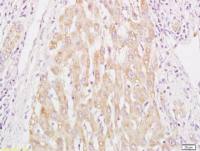

| 产品图片 | ![]() Paraformaldehyde-fixed, paraffin embedded (rat brain tissue); Antigen retrieval by boiling in sodium citrate buffer (pH6.0) for 15min; Block endogenous peroxidase by 3% hydrogen peroxide for 20 minutes; Blocking buffer (normal goat serum) at 37°C for 30min; Antibody incubation with (PTEN(Ser385)) Polyclonal Antibody, Unconjugated (bs-20195R) at 1:400 overnight at 4°C, followed by operating according to SP Kit(Rabbit) (sp-0023) instructionsand DAB staining. ![]() Blank control (blue line): A431 cells (fixed with 70% methanol (Overnight at 4℃) and then permeabilized with 90% ice-cold methanol for 20 min at -20℃). Primary Antibody (green line): Rabbit Anti-Phospho-PTEN(Ser385) antibody (bs-20195R),Dilution: 3μg /10^6 cells; Isotype Control Antibody (orange line): Rabbit IgG . Secondary Antibody (white blue line): Goat anti-rabbit IgG-FITC,Dilution: 1μg /test. |